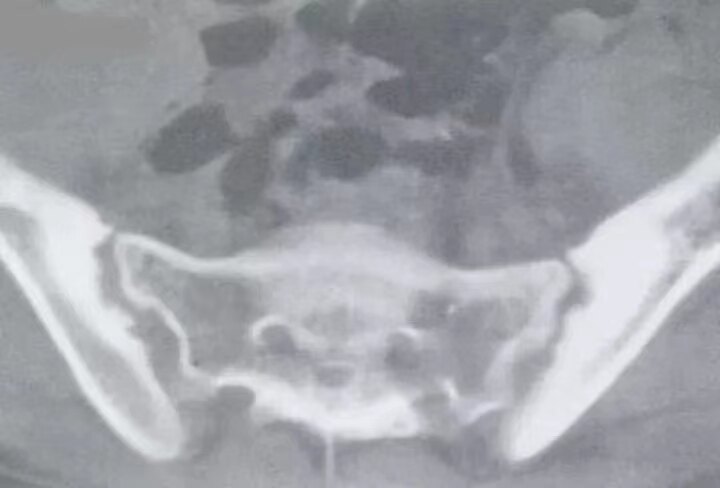

图注:双侧骶髂关节,骨质破坏,髂骨侧软骨下致密硬化伴囊变,关节间隙狭窄。

图注:CT示双侧骶髂关节面对称性骨质侵蚀破坏,粗糙不光滑,关节面致密硬化。